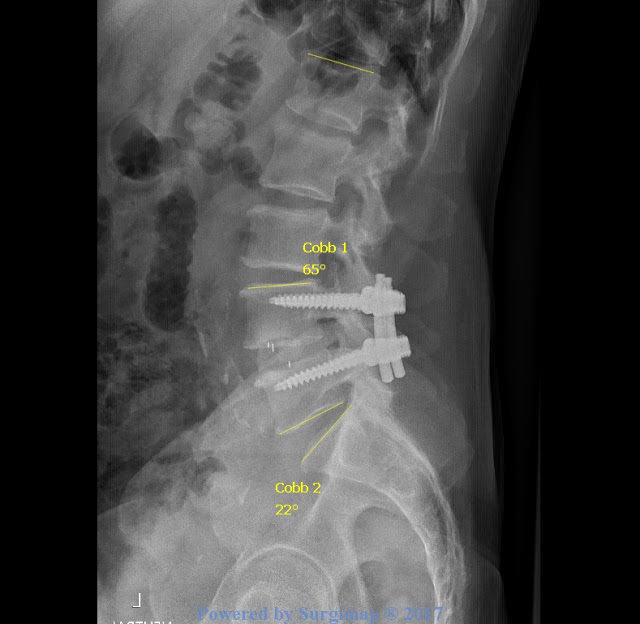

The investigators of the study used the Cobb method to take disk height, segmental coronal alignment, and segmental lordosis measurements from x-rays. (Again, segmental lordosis refers to the vertebrae of the spine where the spinal fusion was performed.) The investigators of the study took the measurements at the following times:

t0: x-rays taken on the day of surgery

t1: x-rays taken at patient's first postoperative follow-up (the average time for both the c-TLIF and TLIF group was six weeks)

t2: one year follow-up

t3: final follow-up (c-TLIF group: average final follow-up time was 26 months; TLIF group: average final follow-up time was 22 months)